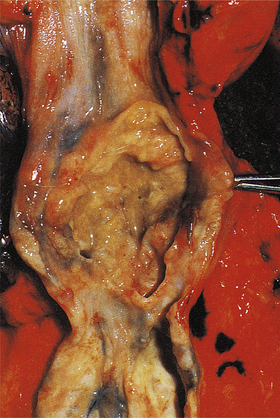

Carcinoma of the oesophagus, either squamous or adenocarcinoma, usually commences as an ulcer, but spreads to become annular and constricting so that the patient develops dysphagia (difficulty in swallowing) (Fig. 15.5). However, by the time most patients present, direct spread outside the oesophagus has occurred and the surgical resection rate is only about 40%. Resectability and ultimate survival can be improved by pre-operative chemo-irradiation. Those patients who cannot be surgically treated may undergo chemo- or radiotherapy alone, or receive palliative laser therapy. Unfortunately, a substantial proportion of patients are simply intubated to facilitate adequate nutrition. The long-term outlook is therefore very poor; only 5% survive for 5 years. Most patients die from local disease and bronchopneumonia exacerbated by malnutrition. Unlike many forms of cancer, metastases are uncommon at autopsy.

image

Fig. 15.5 Carcinoma of the oesophagus. The oesophagus has been opened to reveal an ulcerated tumour partly obstructing its lumen. Blood loss from the ulcerated surface can lead to anaemia, and the partial obstruction causes dysphagia.